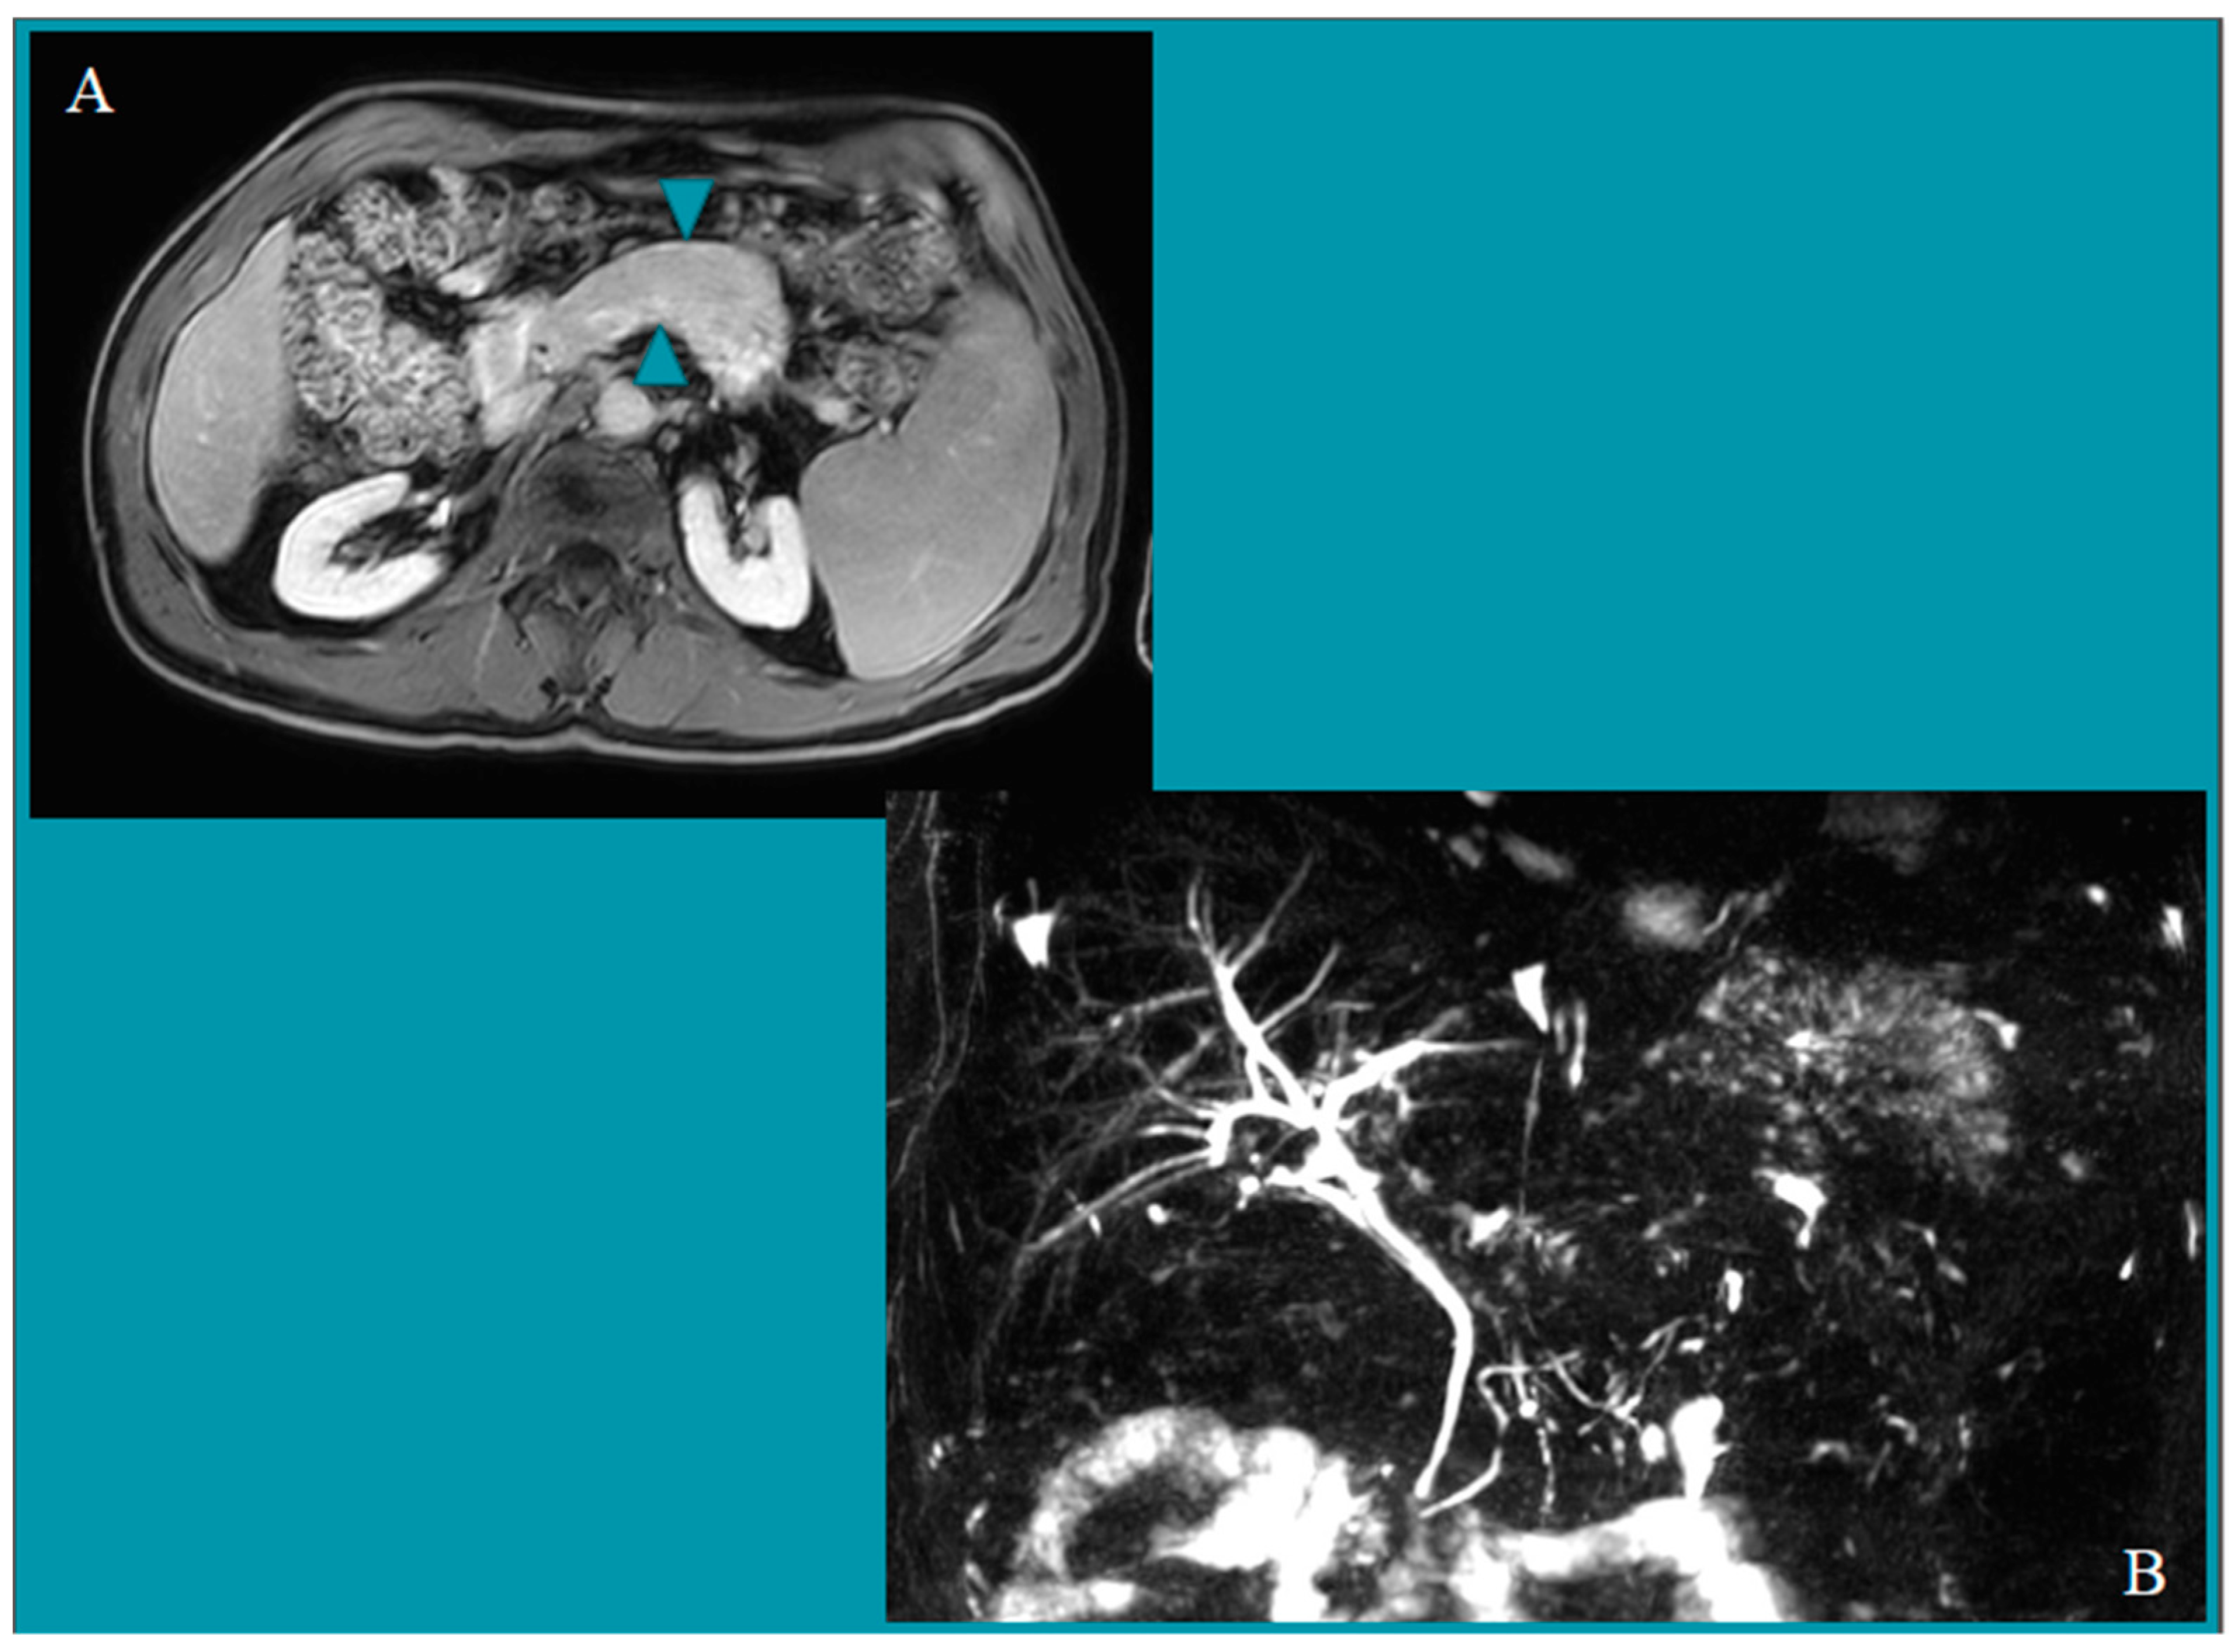

| Group 1 | 72 | 0 | 0 | 0 | Grade A lesions * | 1.4% (0.0–7.5) |

| Group 2 | 71 | 1 | 0 | 1 | Grade B1 lesions | 2.4% (0.0–7.6) |